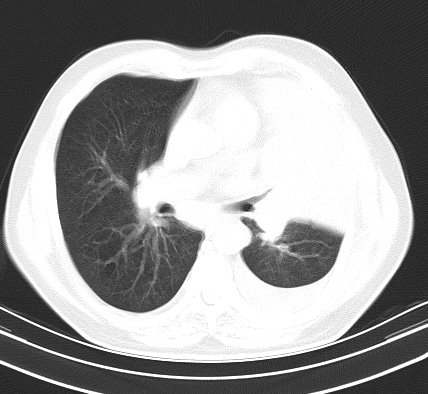

以下是引用老爱克斯新网客在2008-7-31 6:30:00的发言:[br]左肺上叶大片状病灶,左肺上叶支气管狭窄呈鼠尾状,左肺门增大,纵隔内见肿大淋巴结,左侧胸腔积液,余肺清晰。左肺中心型肺癌淋巴结转移,

以下是引用zjb在2008-7-31 6:32:00的发言:[br]左侧中心性肺癌 阻塞性肺炎 肺不张 胸腔积液 建议气管镜

以下是引用zjzjr在2008-7-31 8:45:00的发言:[br]考虑左侧中心性肺癌伴阻塞性肺炎,左肺上叶肺不张,纵隔淋巴结转移;左侧胸腔积液。建议行纤支镜检查。

以下是引用sdzyy在2008-7-31 8:47:00的发言:[br]病灶较治疗前有所进展,胸水增多, 左侧中心性肺癌 并 阻塞性肺炎 肺不张 胸腔积液 可能性大; 建议气管镜检查。 [br] [br]